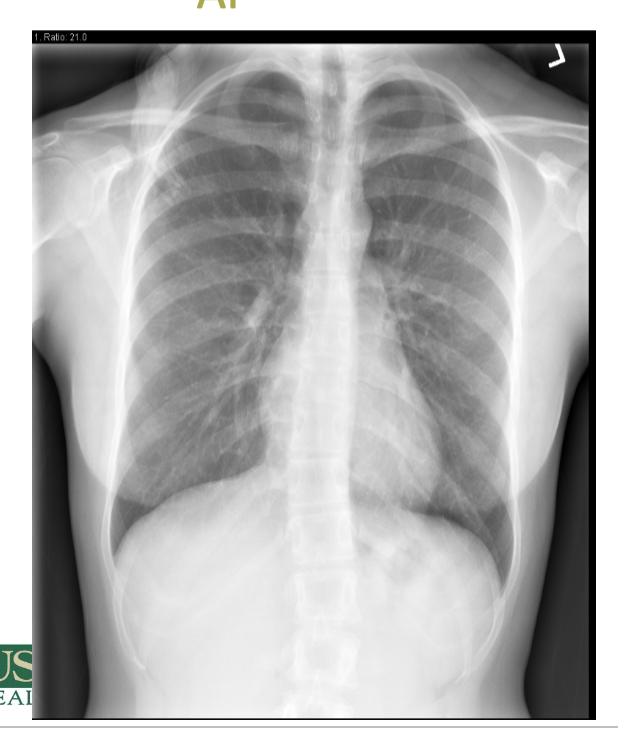

which type of projection is attached?

AP

why might AP views not be as ideal for chest x rays?

AP views can distort heart size and shape due to magnification. They may also obscure some lung structures. also doesn’t show all of the thoracic structures

lung expansion/volume (should count 10 rubs posterior rib bilaterally), if one lung is larger than the other and are there areas of density, look at the crisp costophrenic angles - trace the lateral margins of lung to costophrenic angle. should look at the hemidiaphragms, and the cardiac borders (should be able to clearly see the L and R heart borders)